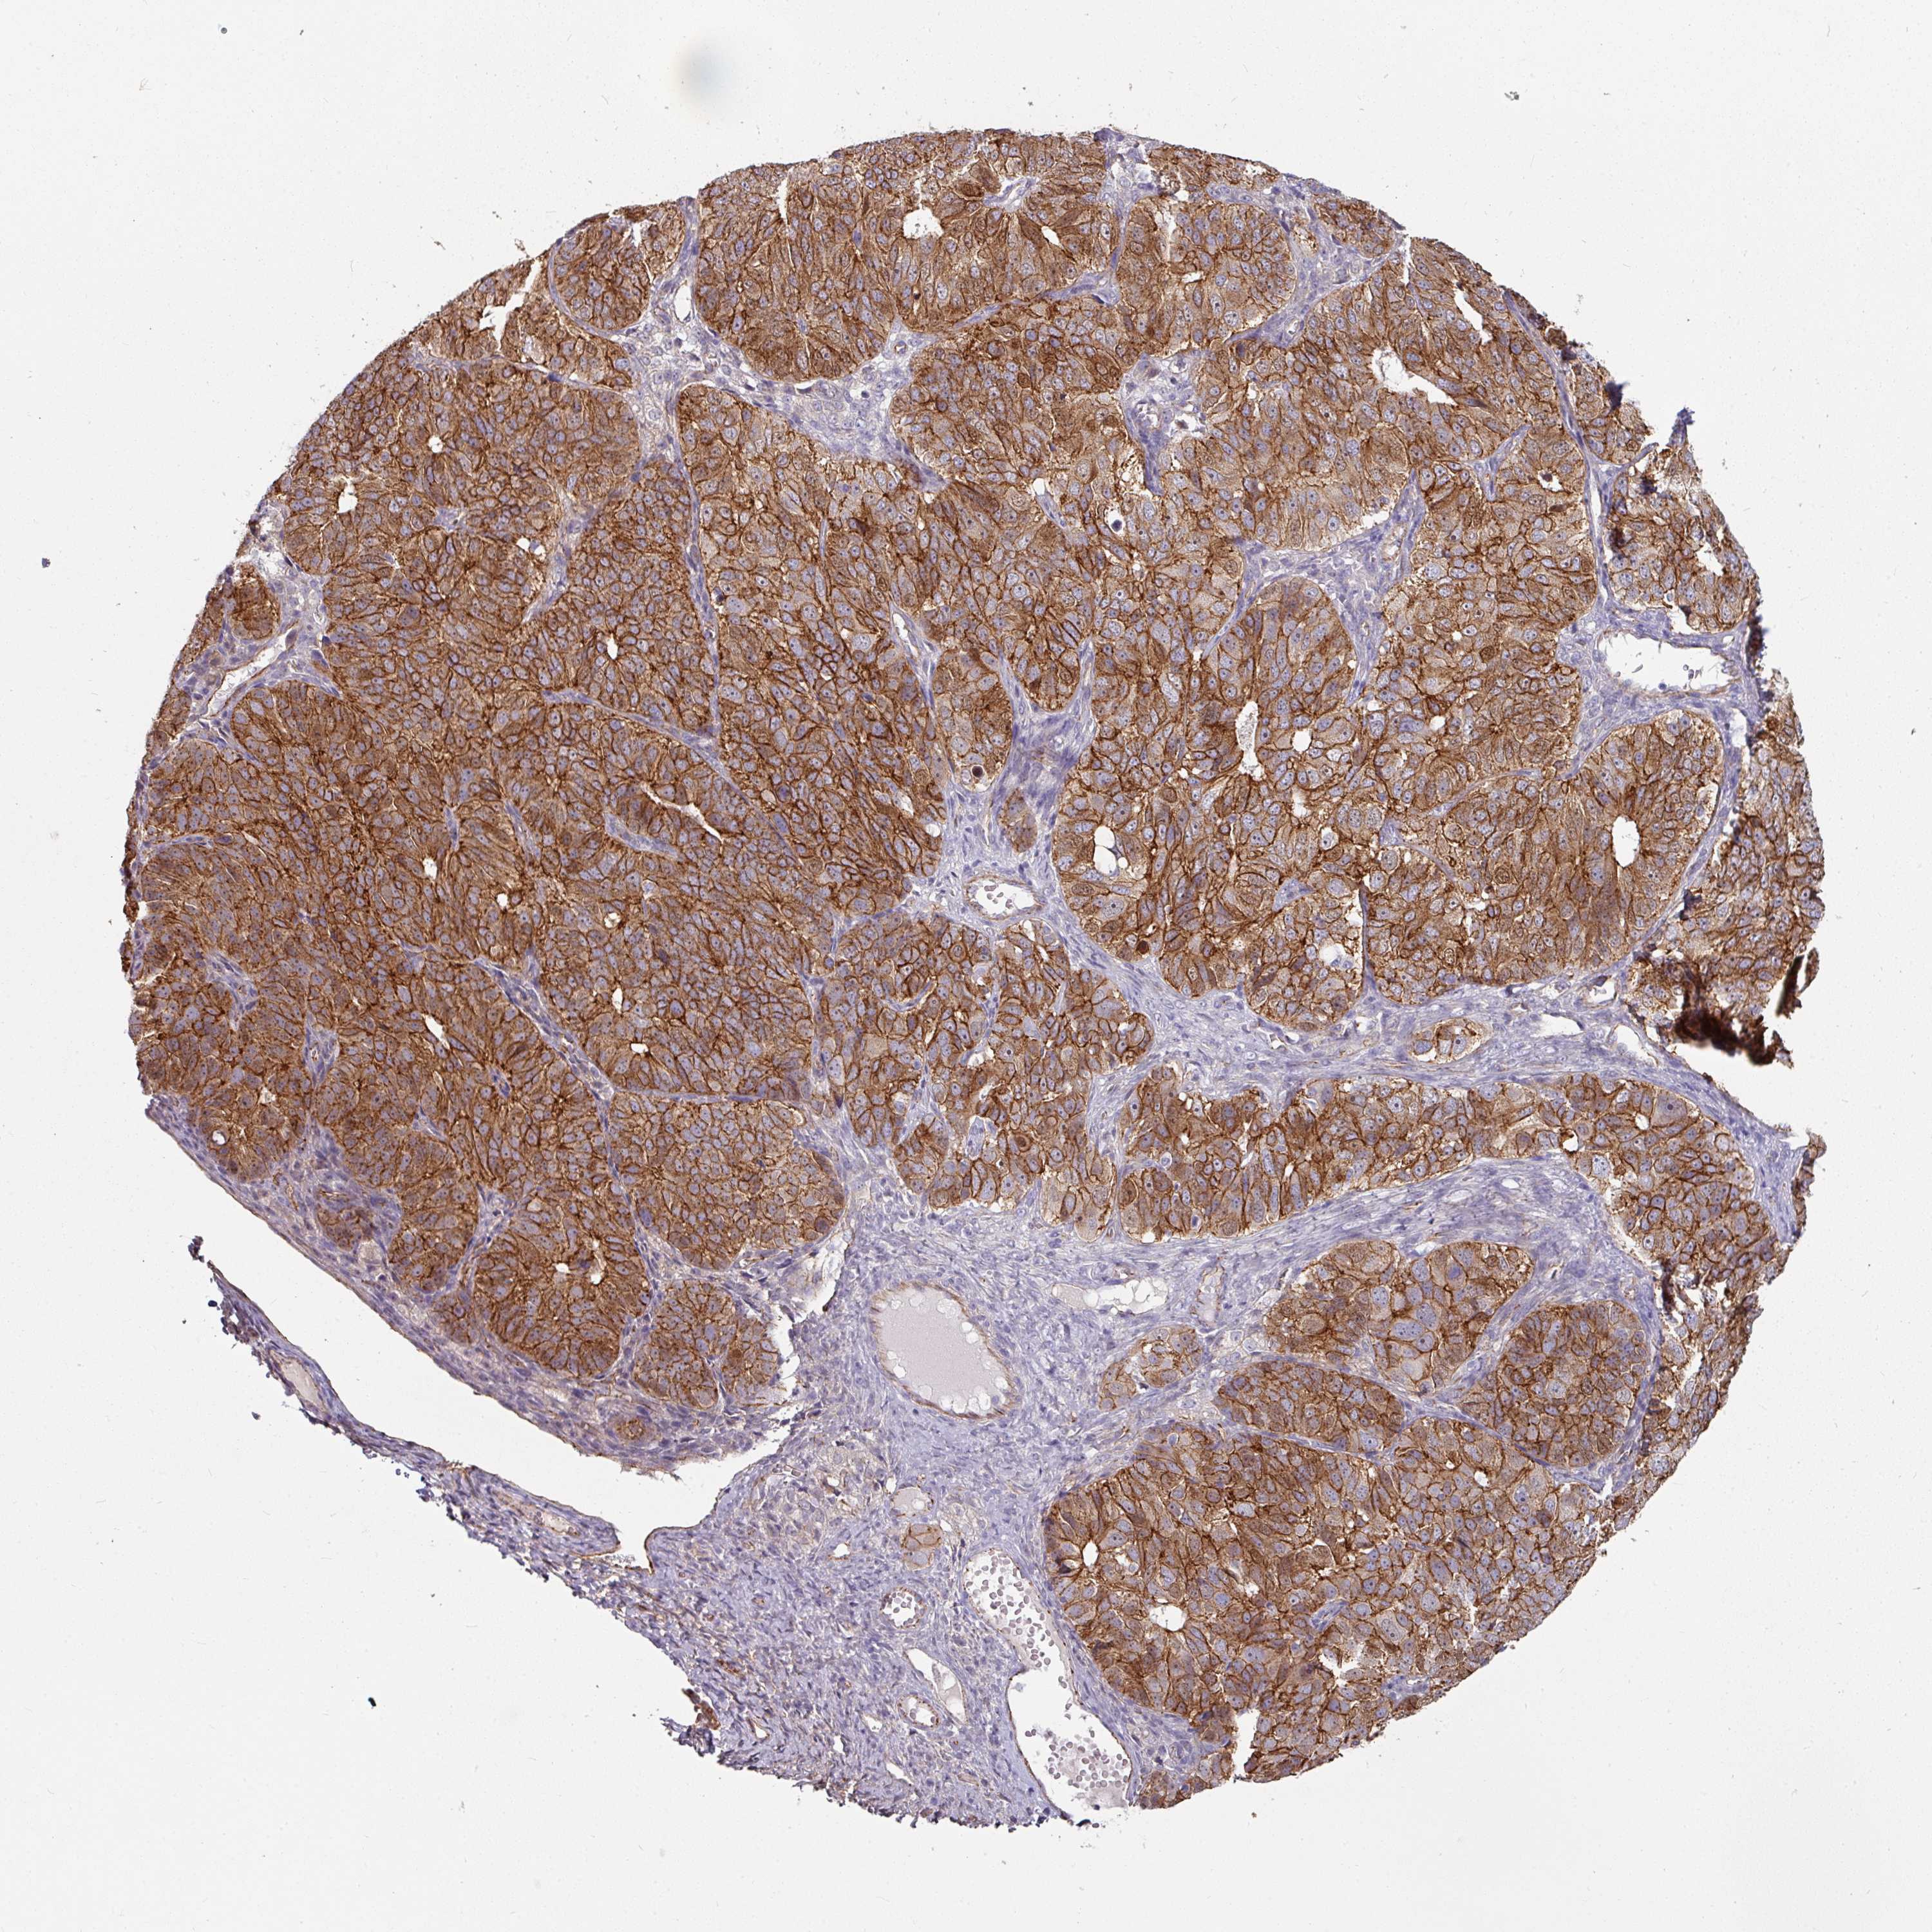

OVARIAN CANCER - Protein expressioni

A mouse-over function shows sample information and annotation data. Click on an image to view it in a full screen mode. Samples can be filtered based on level of antibody staining by selecting one or several of the following categories: high, medium, low and not detected. The assay and annotation is described here.

Note that samples used for immunohistochemistry by the Human Protein Atlas do not correspond to samples in the TCGA dataset.

Antibody stainingi

Antibody staining in the annotated cell types in the current human tissue is reported as not detected, low, medium, or high, based on conventional immunohistochemistry profiling in selected tissues. This score is based on the combination of the staining intensity and fraction of stained cells.

Each image is clickable and will lead to virtual microscopy that enables deeper exploration of all samples and also displays staining intensity scores, fraction scores and subcellular localization as well as patient and tissue information for each sample.

Antibody HPA032047

Antibody CAB002139

Staining

High

Medium

Low

Not detected

Intensity

Strong

Moderate

Weak

Negative

Quantity

>75%

75%-25%

<25%

None

Location

Nuclear

Cytoplasmic/membranous

Cytoplasmic/membranous,nuclear

Cystadenocarcinoma, serous, NOS

Carcinoma, endometroid

Cystadenocarcinoma, mucinous, NOS

Carcinoma, NOS